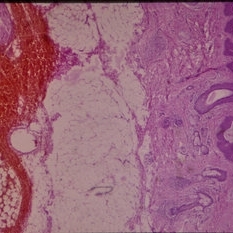

Histopathology of Linear Sebaceous Nevus Syndrome

Histopathology of Linear Sebaceous Nevus Syndrome

Feb 20 2015 by H. Michael Lambert, MD

Histopathology of linear sebaceous nevus syndrome.

Condition/keywords: histopathology, linear nevus sebaceous syndrome